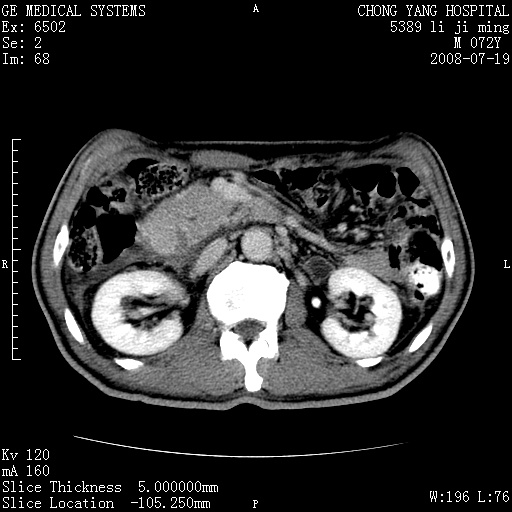

以下是引用zjzjr在2008-7-19 20:57:00的发言:[br]胰头增大,边缘模糊,周围可见渗出影,右侧肾前筋膜增厚.支持胰腺炎.

以下是引用yangyudong333在2008-7-20 6:56:00的发言:[br]胰腺增大尤以胰头明显,边缘模糊,周围可见渗出影,右侧肾前筋膜增厚,肠管於涨.支持胰腺炎

以下是引用不学无术在2008-7-19 23:15:00的发言:[br]胰腺增大尤以胰头明显,边缘模糊,周围可见渗出影,右侧肾前筋膜增厚,肠管於涨.支持胰腺炎